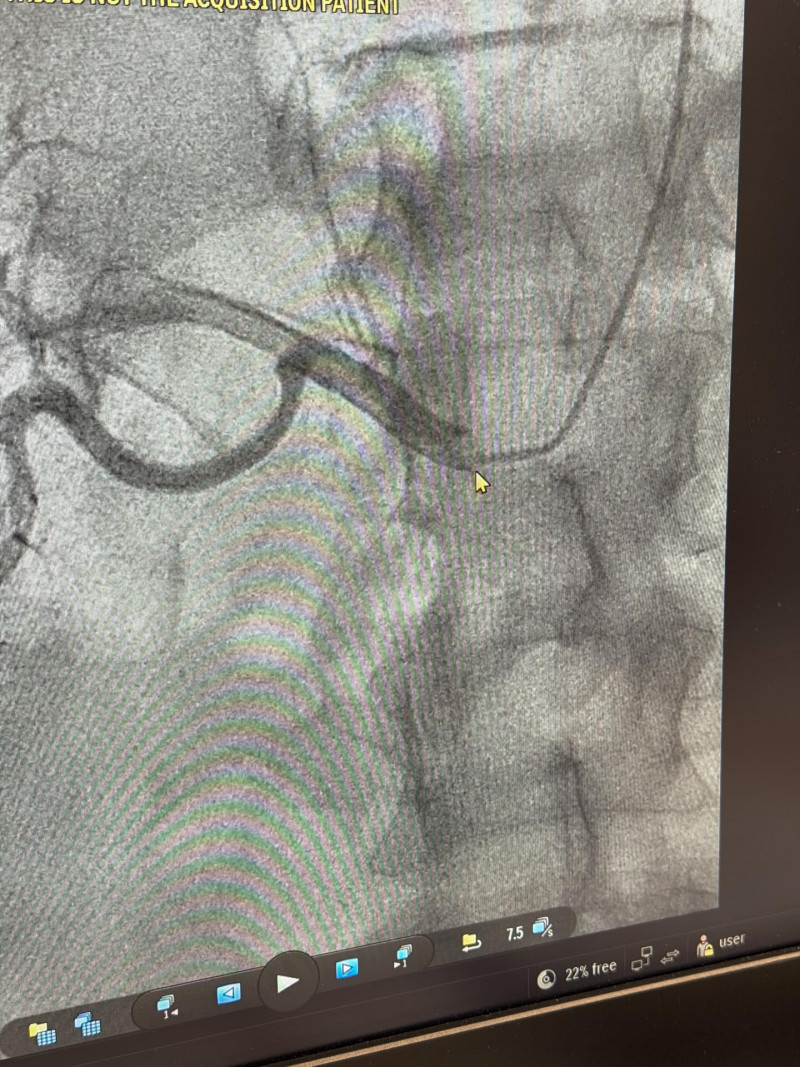

У Володимирському ТМО проводять ангіографію ниркових артерій — високоточне обстеження, яке допомагає виявити звуження, аневризми чи тромбози судин і визначити причину неконтрольованої артеріальної гіпертензії. Процедура мінімально інвазивна, безпечна та дає лікарю точні дані для вибору ефективного лікування.

Через катетер у судину вводиться рентгенконтрастна речовина, завдяки якій артерії стають чітко видимими. Ангіограф дозволяє отримати детальне зображення судин у реальному часі та оцінити їхній стан з максимальною точністю.

Особливою перевагою є ендоваскулярні технології: у разі потреби лікар може не лише діагностувати проблему, а й одразу виконати лікувальне втручання, наприклад стентування звуженої судини.